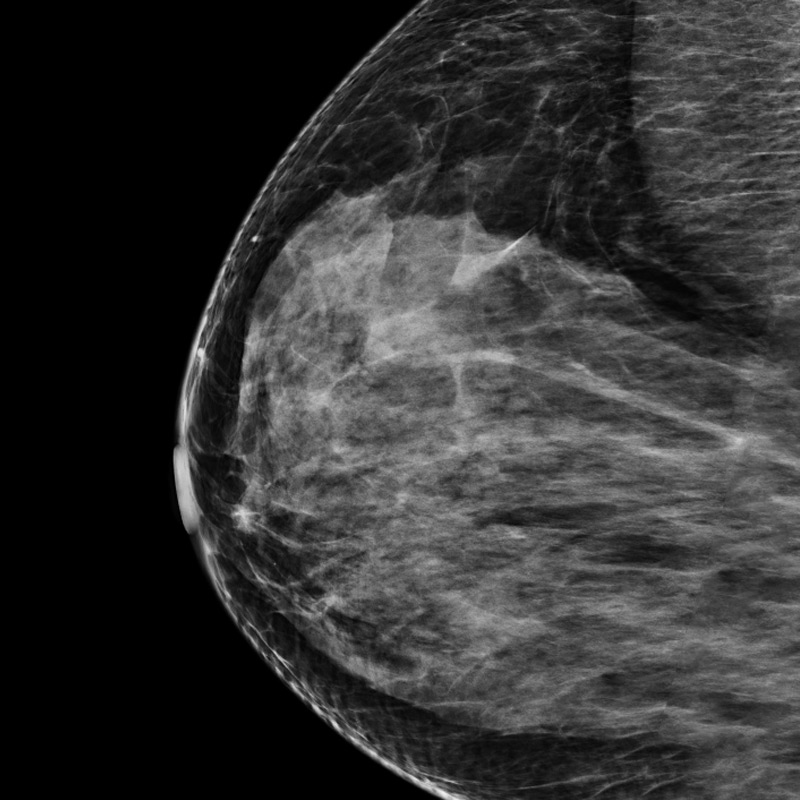

The future of breast cancer prevention is here

A new AI-based imaging technology can predict a patient’s future breast cancer risk by analyzing subtle patterns in a standard mammogram. Developed by WashU Medicine researchers and recently acquired by a leading medical AI company, this tool promises to save more lives through earlier, more personalized prevention.